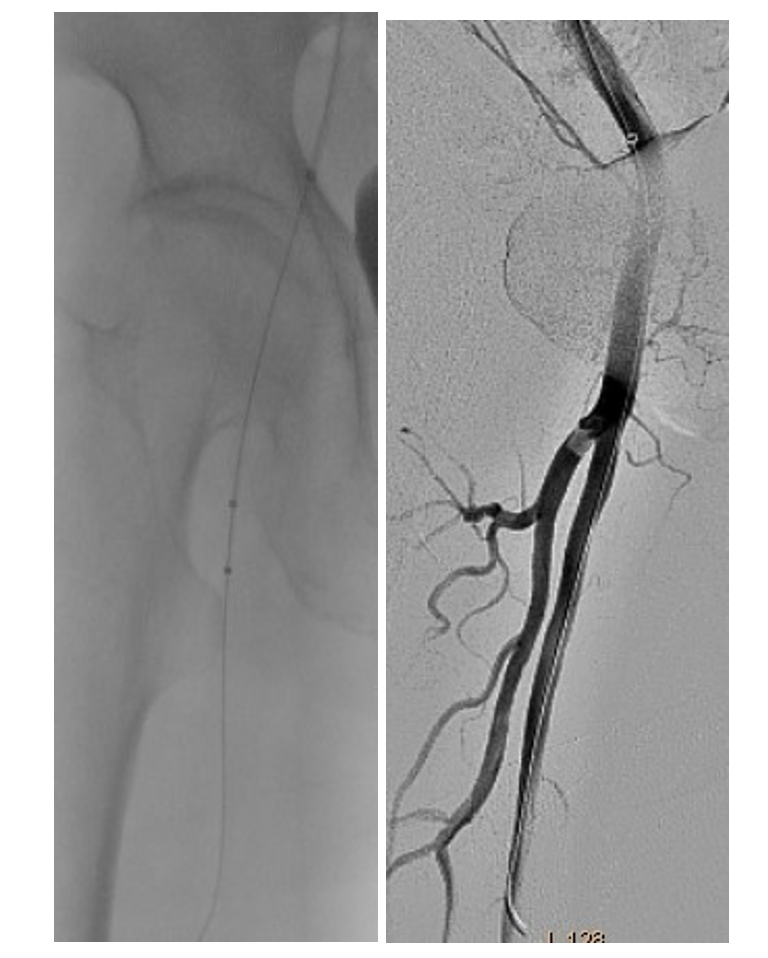

The angiography was performed via the left common femoral artery. The diagnostic catheterization of the right upper limb showed a thrombus in the origin of the right brachial artery, second level of thrombosis in the brachial bifurcation into its ulnar and radial branches, and poor distal filling of the radial artery (Figure 1).

The diagnostic catheterization of the right lower extremity showed a “riding” thrombus at the bifurcation of the superficial femoral artery (SFA)/profunda femoris artery (PFA) and a long thrombotic occlusion starting from the middle segment of the SFA involving the popliteal artery and tibiofibular trunk (Figure 2). In the setting of simultaneous acute limb ischemia (ALI) of the right upper and lower limbs, we performed ad hoc concomitant percutaneous transluminal thrombectomy (PTA).